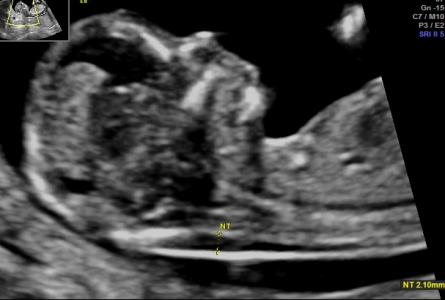

Naszym atutem jest również profesjonalny sprzęt ultrasonograficzny oraz nowoczesne wyposażenie gabinetów, którymi dysponujemy na co dzień.

Arkadiusz Krzyżanowski - na codzień pracuję w Katedrze i Klinice Położnictwa i Patologii Ciąży (Szpital SPSK1 - Staszica 16) Uniwersytetu Medycznego w Lublinie, gdzie oprócz opieki nad pacjentami w zakresie Położnictwa, Patologii Ciąży i Perinatologii zajmuję się dydaktyką studentów Wydziału Lekarskiego naszego Uniwersytetu jak i pracą badawczą. Moje najważniejsze osiągnięcia to: Doktorat z zagadnień porodu przedwczesnego, Habilitacja z zakresu pogłebionej diagnostyki prenatalnej oraz zaawansowanych badań nad komórkami macierzystymi. Jestem autorem i współautorem ponad 180 doniesień i publikacji, w tym 86 artykułów o charakterze naukowym jak i dydaktycznym w renomowanych czasopismach - wielu o zasięgu międzynarodowym. Moje zainteresowania wynikają z mojej pasji - chęci niesienia pomocy.

Perinatologia zwana też medycyną matczyno-płodową jest dziedziną medycyny zajmującą się opieką nad dzieckiem jeszcze w okresie płodowym. Celem tej opieki jest określenie najwłaściwszego sposobu prowadzenia ciąży czy możliwości wykonania ratujących życie zabiegów chirurgicznych w przypadku wykrycia w badaniach prenatalnych wady u płodu.

Dostępność badań, nowoczesny sprzęt diagnostyczny oraz specjalistyczna wiedza umożliwiają wychwycenie pewnych wad wrodzonych. Należy podkreślić, że niestety nie zawsze i nie wszystkich. Czasami możliwe jest leczenie jeszcze przed narodzinami.